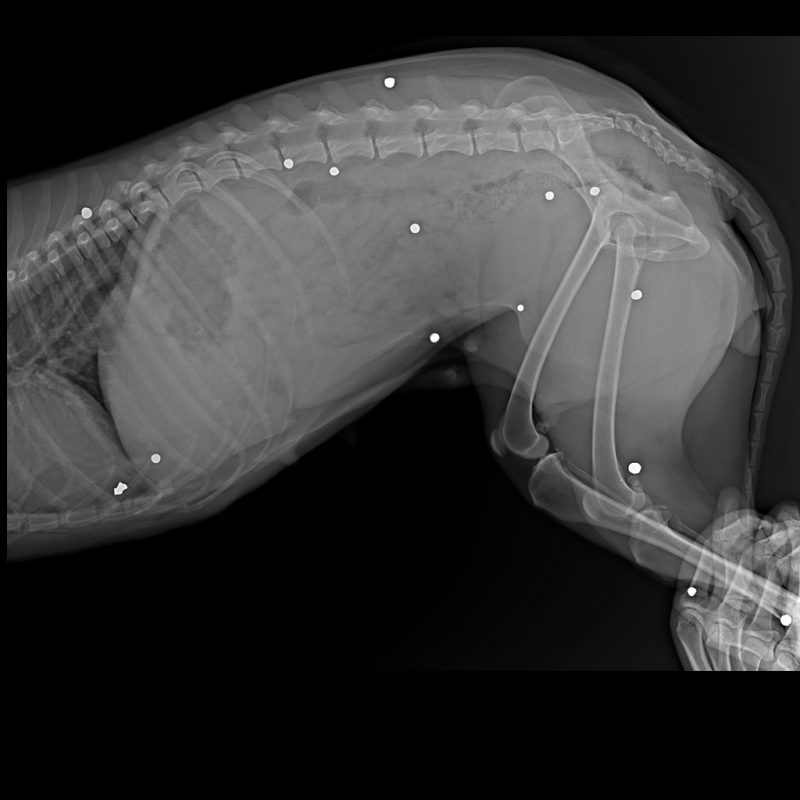

Каля мястэчка Сапоцкін знайшлі храмога сабаку. У целе жывёлы праз рэнтген выявілі больш за 20 куль. Адну з іх выцягнулі падчас аперацыі. Валанцёры шукаюць, хто страляў у сабаку.

Інцыдэнт адбыўся восенню 2021 года, магчыма раней. У сабакі пашкоджанні, зробленыя з выкарыстаннем агнястрэльнай альбо пнеўматычнай зброі, дапускаюць валанторы.